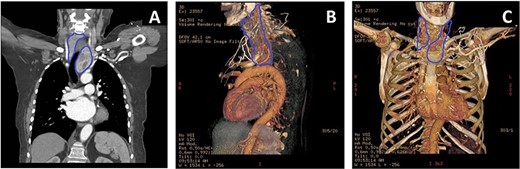

(A) CT thorax showing the extension of the retrosternal goitre (blue outline), causing tracheal deviation with extension and abutting the distal ascending aorta and arch. (B) 3D-reconstructed CT thorax lateral view highlighting goitre (blue outline) relationship with respect to ascending aorta and arch, and other mediastinal structures. (C) 3D-reconstructed CT thorax allowed planning of mini-sternotomy in relation to goitre position.

The goitre’s position would invariably make aortic cannulation and cross-clamping to perform the AVR difficult. It was deemed that the goitre needed removal first. However, the retrosternal position meant that normal cervical excision would be challenging and risky. Furthermore, due to the severe nature of the AS, she was considered unsafe to undergo thyroidectomy as a primary procedure. Endocrine surgeons were consulted and consensus dictated that combined procedure would be the best approach utilizing a mini-J sternotomy to aid in excision of the hemi-goitre prior to completing the AVR. 3D imaging was reconstructed to determine the anatomical relations in detail and plan the combined surgical approach meticulously (Fig. 2B and C).